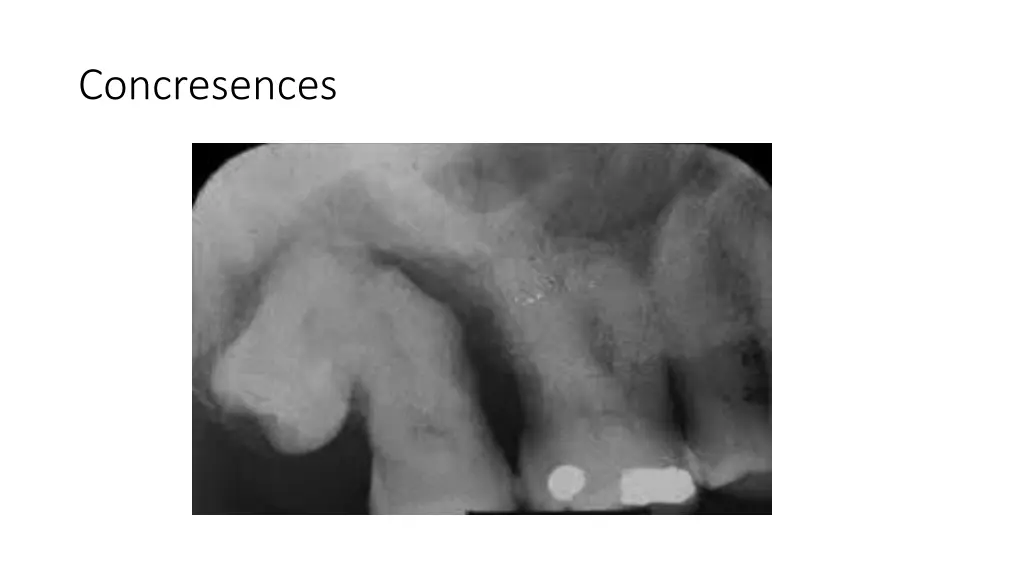

True Anodontia, Partial True Anodontia, Partial False Anodontia, Mesiodens/Supernumerary, Microdontia, Marcrodontia, Gemination/Right Fusion/Left, Peg-Lateral, Fusion Two Roots/Two Crowns, Dens in dente, Dilaceration, Concresences, Taurodontia, Hypercementosis, Amelogenesis Imperfecta, Dentinogenesis Imperfecta, Hutchinson Incisors, Mulberry Molars, Mental Foramens - Radiolucent.

Fusion two roots/two crowns